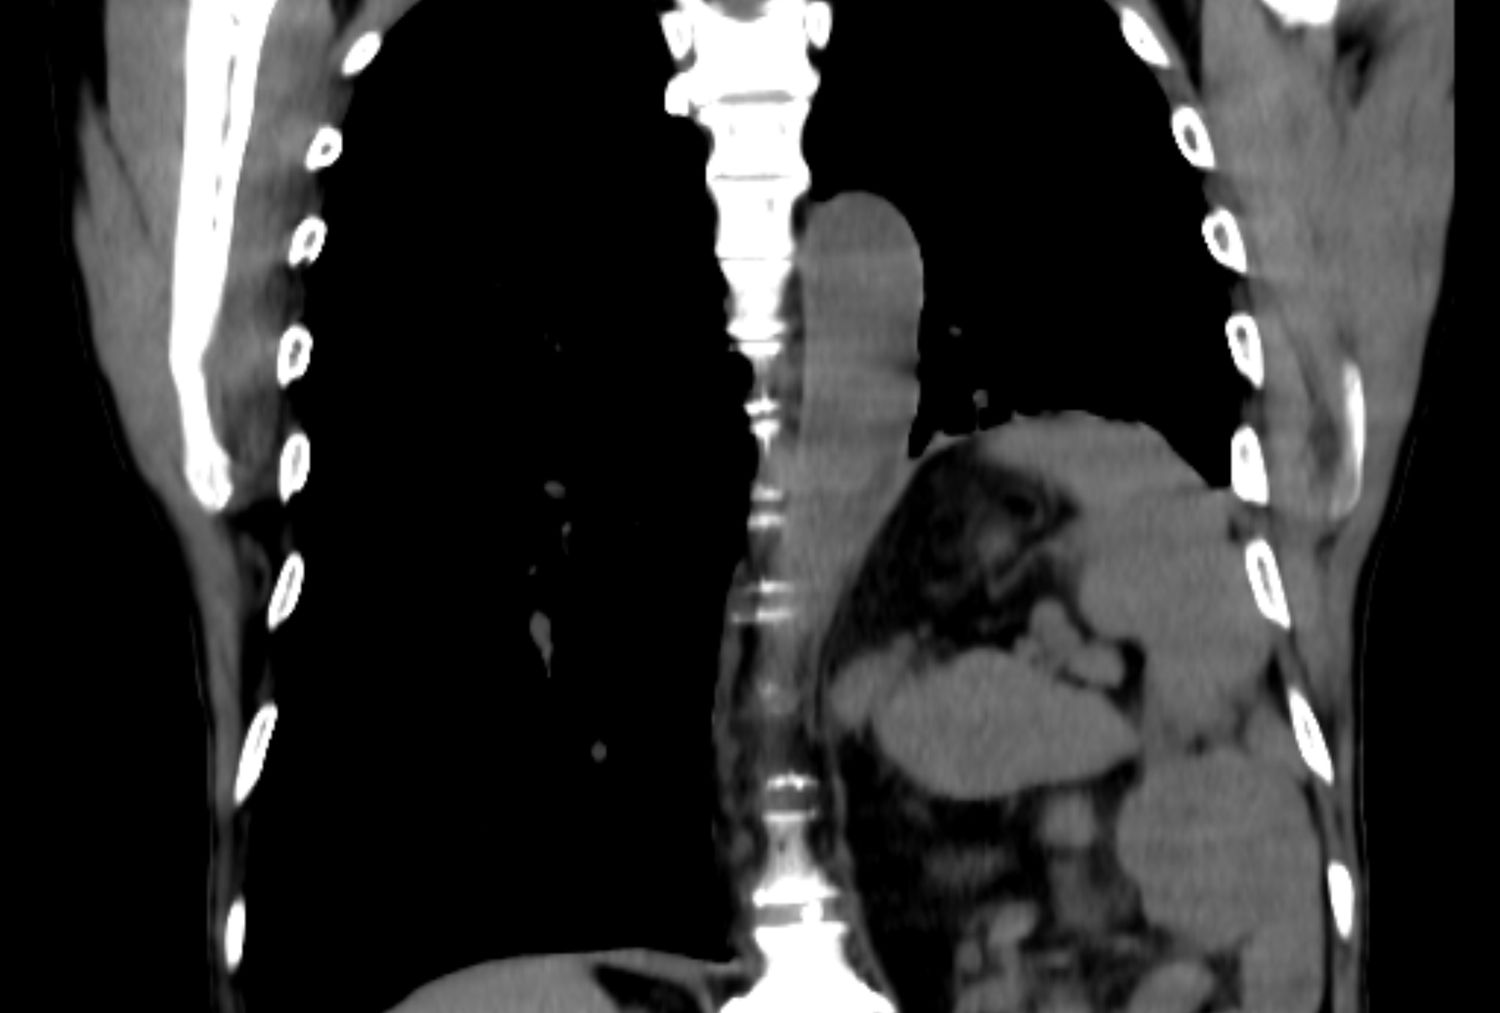

This is how the lungs look on CT – the most effective method for diagnosing lung cancer

— Yearly fluorography as screening for lung cancer does not reduce lung cancer mortality. Of course, on FOG you can see a shadow in the lung, but often small formations are visible, and the point is not in the qualifications of the radiologist, but more often in limiting the ability of the method itself. The only method that has any effect on reducing mortality is low-dose computed tomography of the chest in the high-risk population – over the age of 50 years and with a history of smoking for more than 10 years.

For those patients who come to us with detected formations in the lung, we perform additional examinations, such as bronchoscopy to examine the bronchi with a possible biopsy, ultrasound or CT of the abdominal cavity, MRI of the brain.

— Yes, the pandemic has shown us that lung imaging as screening works: many people with a viral respiratory infection went to private centers and had CT scans of the lungs — and to their surprise, the examination did not reveal viral pneumonia, but a tumor in the lung, oh which people didn’t even know. A number of patients who were diagnosed in such a random way, we have already operated on. So there is no evil without good!